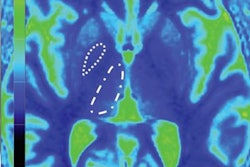

Last but definitely not least, the safety of gadolinium-based contrast agents looks set to be a major issue throughout 2019. A German group has published new findings on this topic in Radiology.